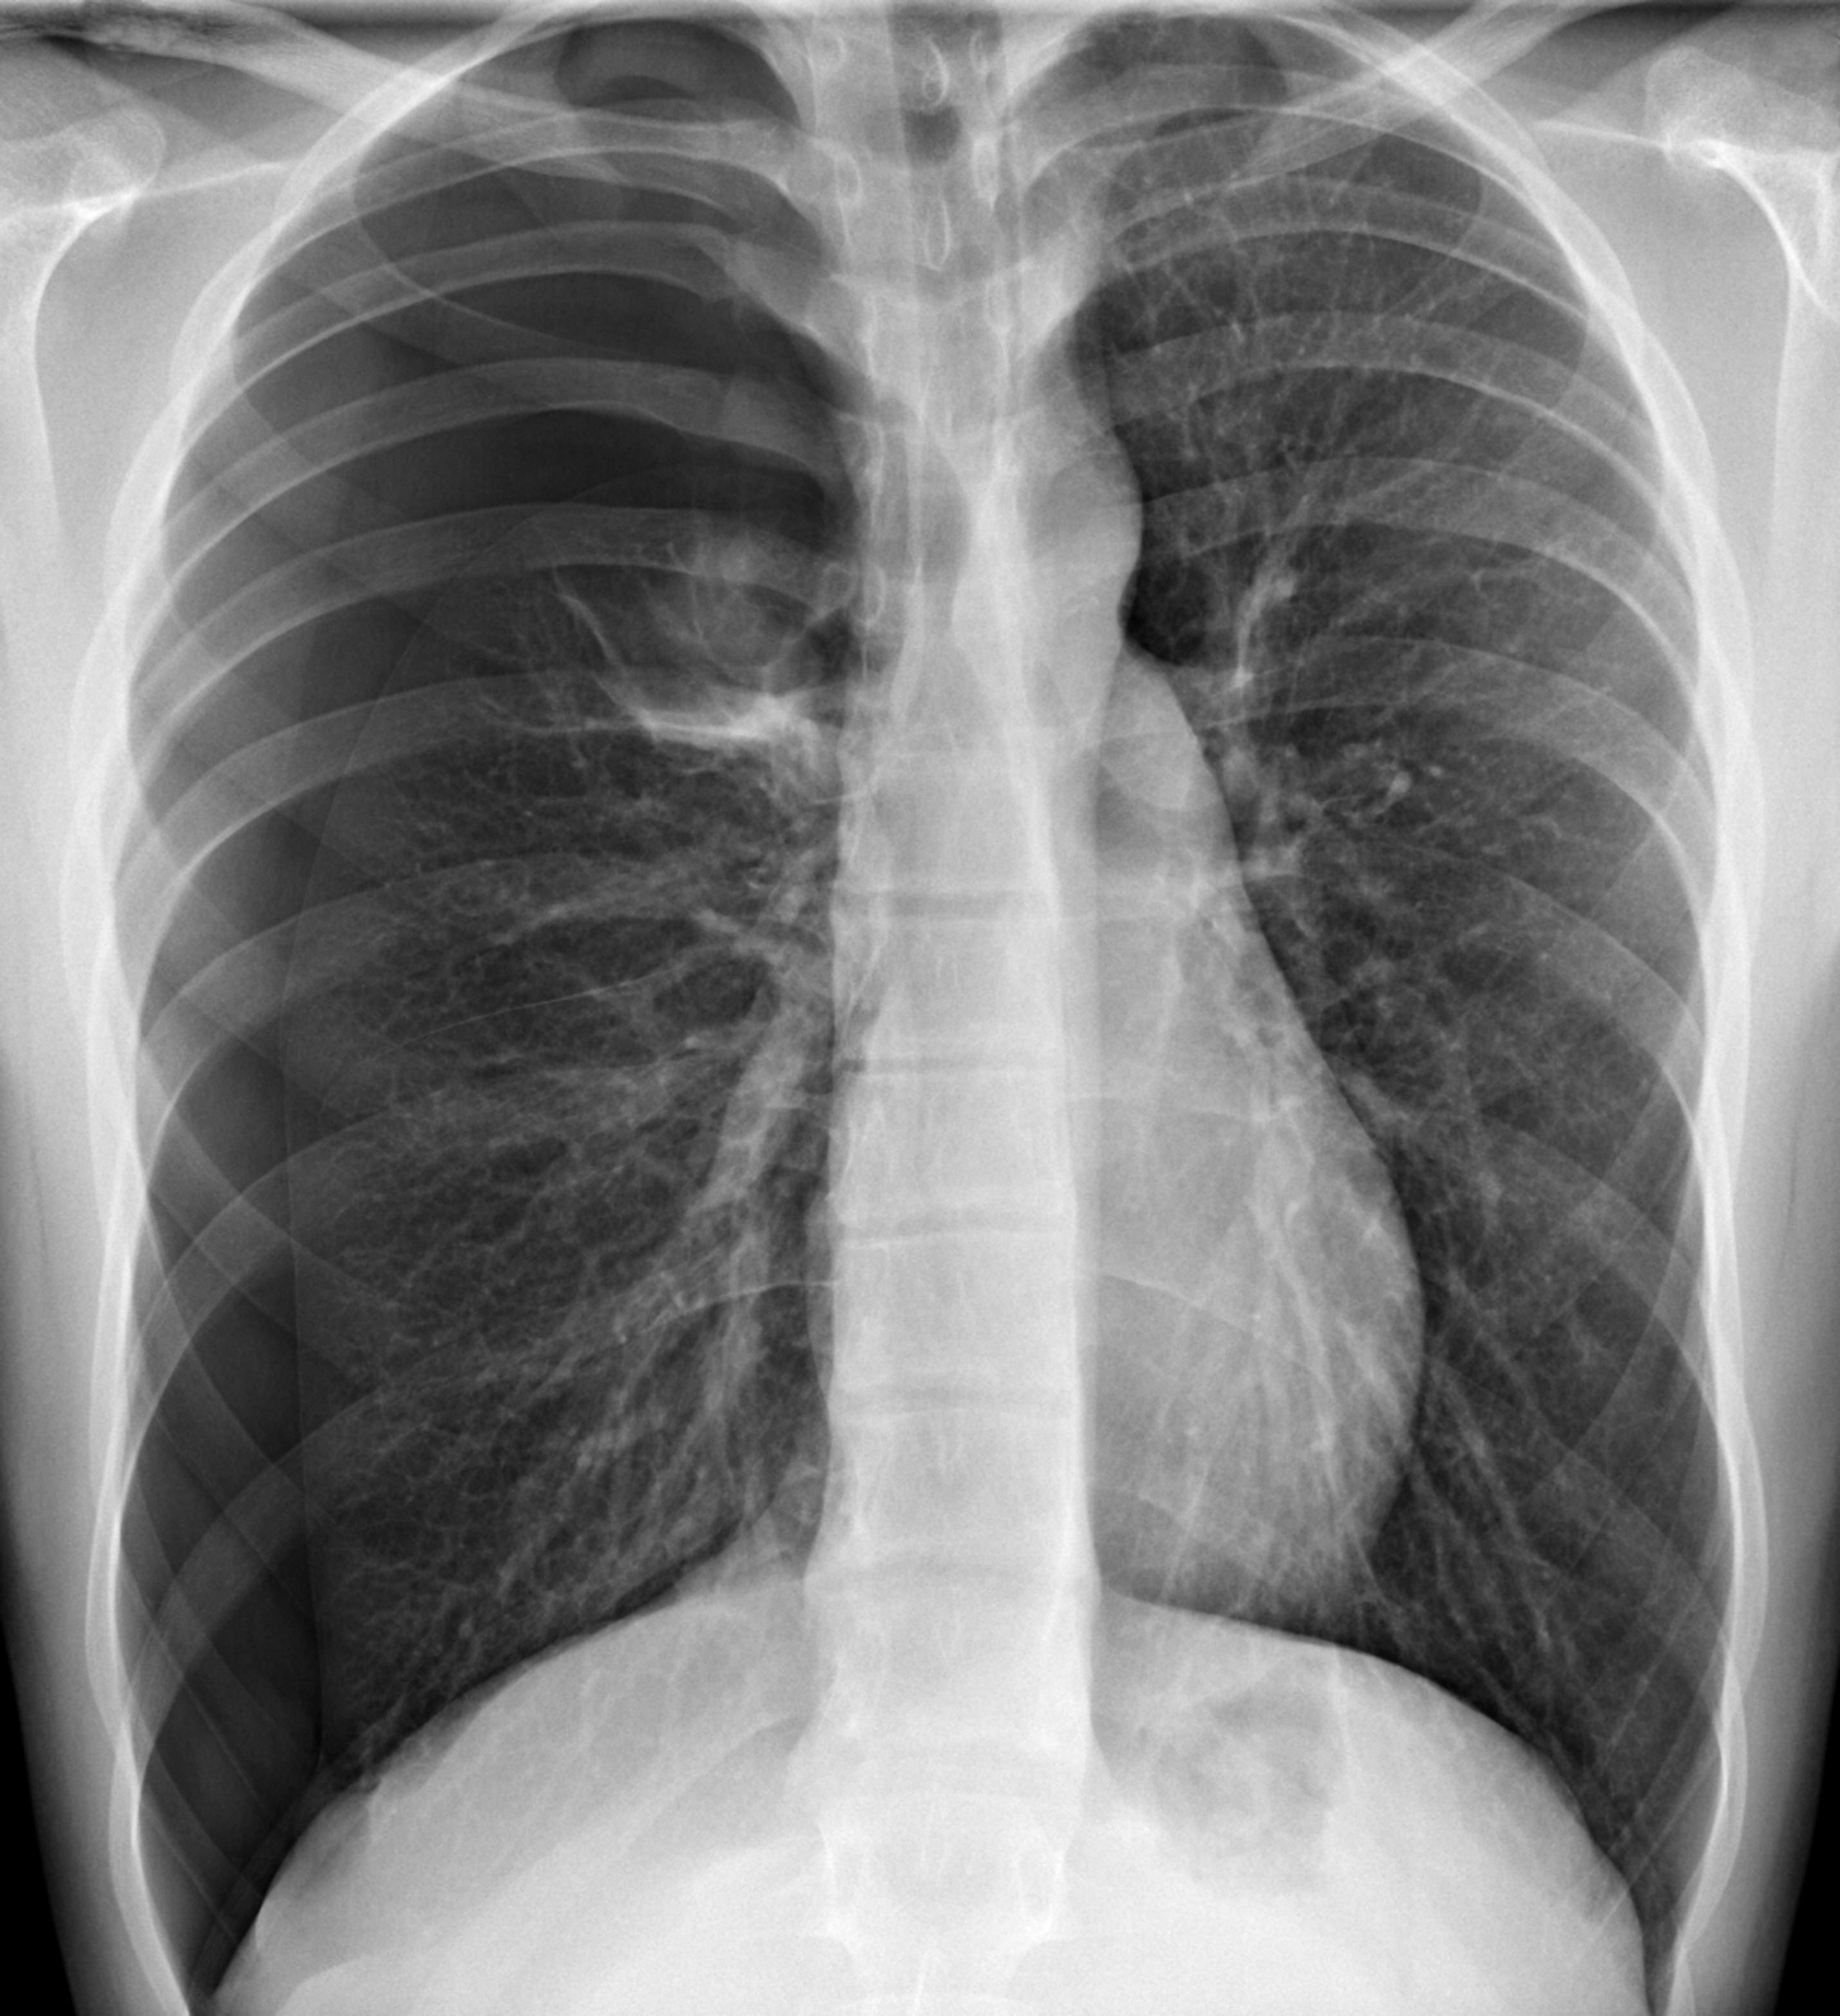

제가 본 학생은 신장(키)이 더 빠르게 생장하다 보면 폐 성장이 늦어지면서 그 빈 공간(흉막강)을 공기가 차게 되는 경우의 케이스였습니다. 폐와 흉각은 흉막이라는 막에 쌓여 있는데, 평소에는 공기 대신 흉막액이 있어야할 공간인 곳이죠. (자발성 기흉.)

흉통과 호흡곤란

- 일차성 자연기흉 : 기존에 폐질환이 없는 건강한 사람에서 발생한 기흉 (키가 크고 마른 사람, 흡연, 대기오염)